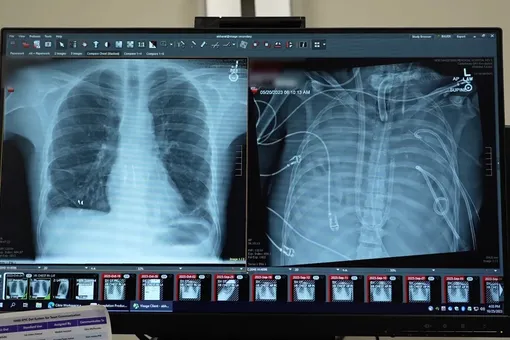

В новой статье, опубликованной в журнале Med, ученые описали случай 33-летнего мужчины, у которого развился острый респираторный дистресс-синдром из-за тяжелого гриппа. Ситуацию осложнила бактериальная инфекция, вызвавшая разрушительную пневмонию. Легкие перестали выполнять свою функцию, а затем начали отказывать сердце и почки. Стандартная терапия уже не помогала.

Обычная пересадка была слишком рискованной – организм был истощен инфекцией. Тогда врачи пошли на крайний шаг: полностью удалили пораженные легкие, чтобы остановить распространение инфекции. Возникла главная проблема – как поддерживать жизнь без органа, который отвечает за насыщение крови кислородом.

Команда создала систему полной искусственной замены легких (total artificial lung, или TAL). Кровь отводилась из правых отделов сердца, проходила через внешний контур, где удалялся углекислый газ и добавлялся кислород, а затем возвращалась в левое предсердие. При этом система регулировала давление и поток крови, чтобы сердце продолжало работать стабильно. В отличие от стандартных аппаратов ЭКМО, эта схема полностью брала на себя функции легких.